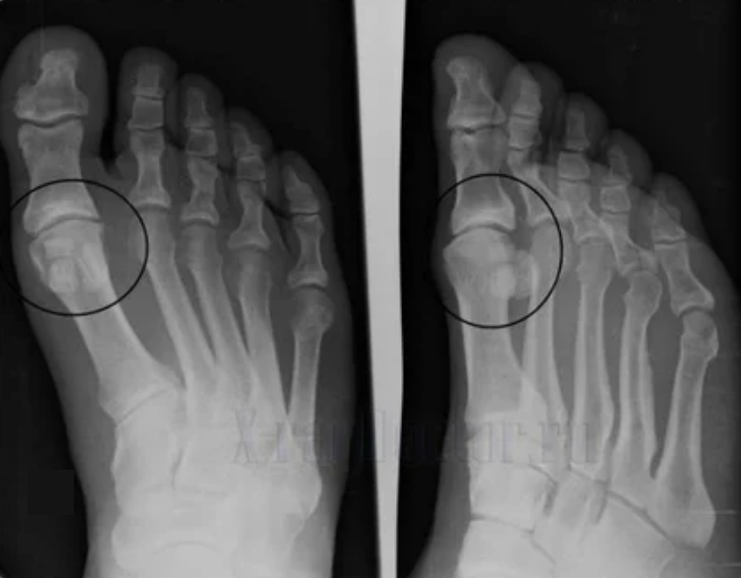

To diagnose Rheumatologists learn the patient's complaints and set an X -Ray exam.Most radiography is used in 2 forecasts.The doctor stares to have dystrophic disorders in the cartilage and bone compounds.If the articular gap is reduced, the bones are deformed or flattened, there are cystic compounds on the surface of the cartilage, osteoophytees are open signs of arthrosis.During the inspection, arthrosis indicates the instability of the combination: the reading of the limbs and subluxation is broken.

Often an X -Ray picture can not give complete information about the state of combination.For a more comprehensive study, calculated tomography is assigned, it becomes effective to explore the bones.MRI is used to learn more soft tissues.